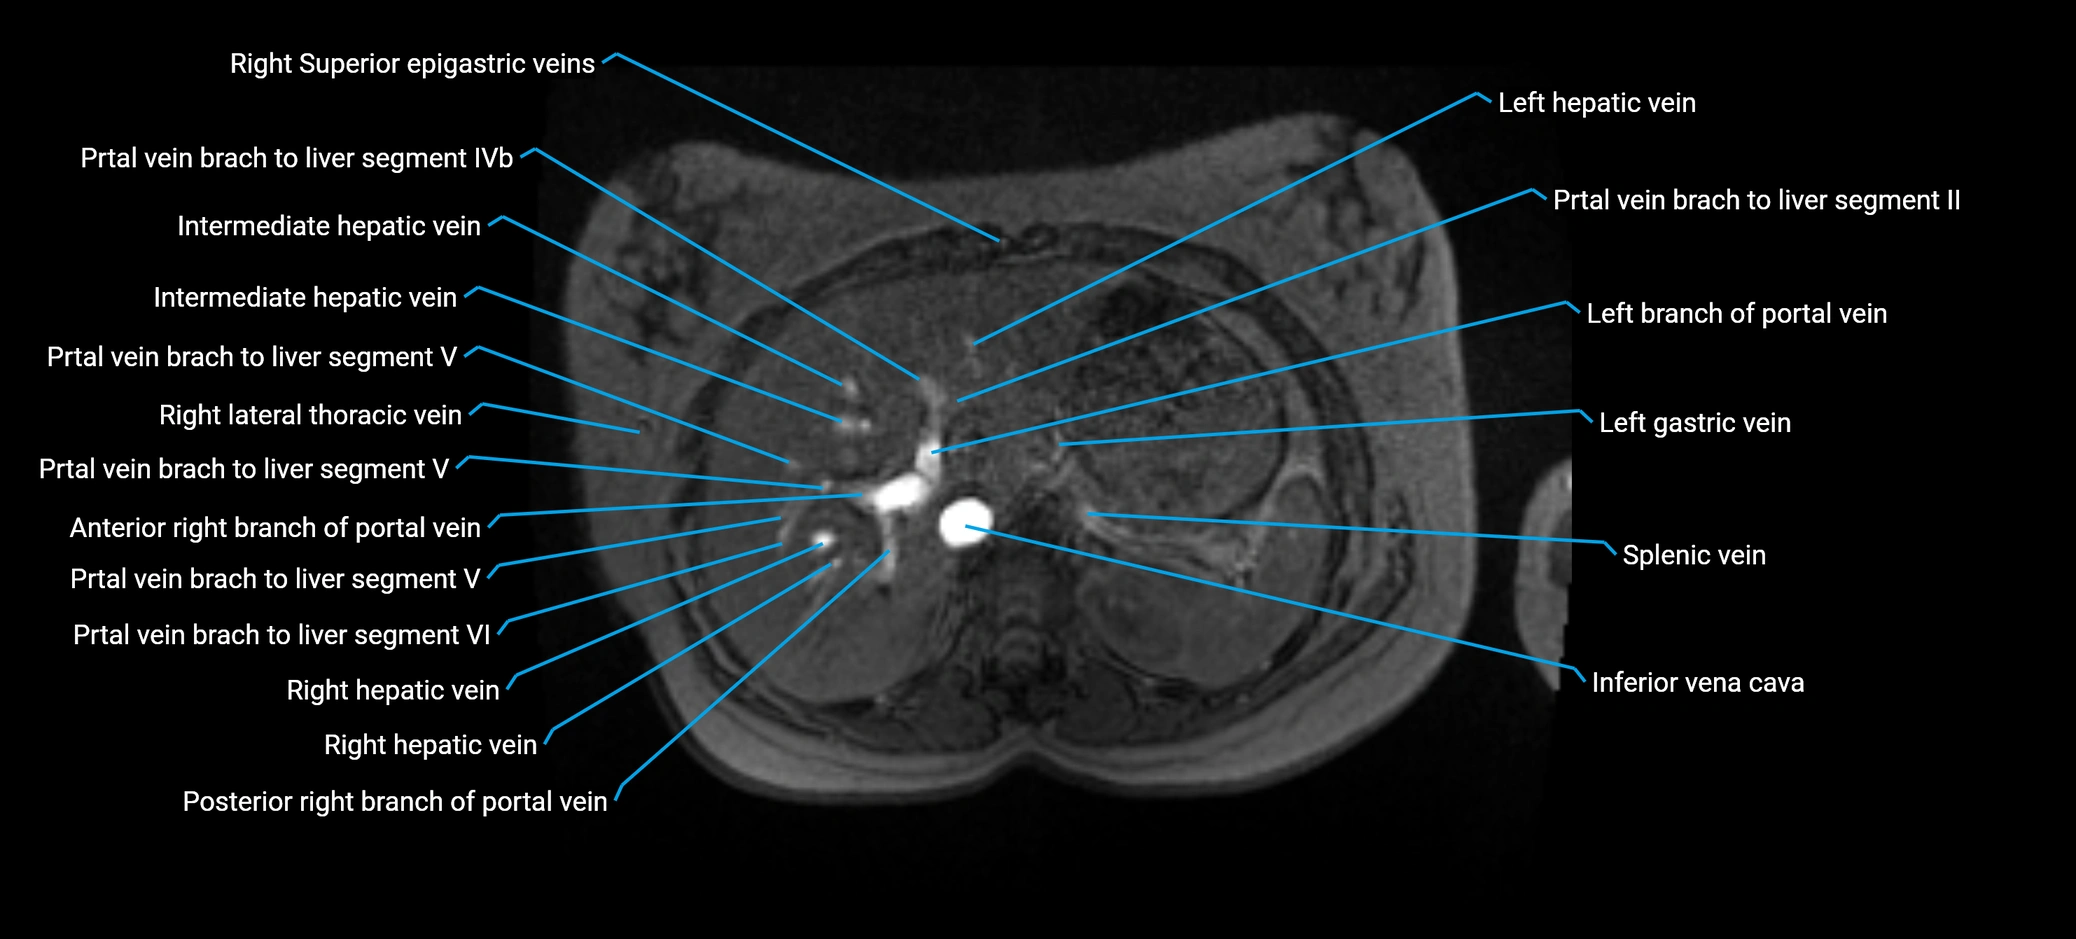

The anterior right branch of the portal vein is a major intrahepatic division of the right portal vein. After the main portal vein bifurcates into right and left branches, the right portal vein divides into anterior and posterior segmental branches.

The anterior right branch supplies the anterolateral liver segments (Segment V) and anteromedial liver segments (Segment VIII) within the right hepatic lobe. It operates as a key vascular route delivering nutrient-rich portal venous blood to the central and superior right liver.

This segmental vasculature is of major importance in hepatic surgery, embolization, segmental resection, transplantation, and imaging-based liver segmentation.

MRV TOF (Time-of-Flight MR Venography):

• Appears as a bright, high-signal vascular channel representing flowing blood

• Clearly shows branching pattern of right portal vein into anterior and posterior branches

• Best in coronal or axial reconstructions for segmental mapping

• No need for contrast, relies on flow-related enhancement

Post-Contrast T1 Fat-Sat GRE:

• Enhances brightly and homogeneously during the portal venous phase

• Clearly delineates branching into segments V and VIII

• Best sequence for evaluating patency, caliber, and anatomic variants

• Early arterial phase: minimal enhancement

• Delayed phase: gradual washout but still brighter than hepatic parenchyma

MRI image

image